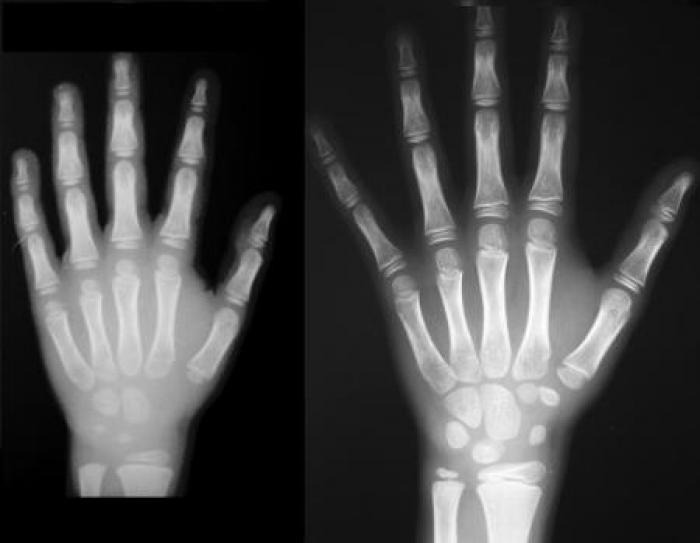

VOLEVA FARE IL FURBO. Si faceva passare per minorenne approfittando dell'aspetto giovanile e, per dimostrarlo, aveva presentato documenti d'identita' falsi. Ma i Carabinieri non gli hanno creduto e l'hanno sottoposto, in ospedale a Sant'Omero, alla radiografia del polso per stabilire l'eta' esatta.

IL FATTO. E' risultato che il bengalese, in realta', ha 18 anni. Per questo e' stato denunciato per false dichiarazioni personali e uso di documenti falsi, Il giovane ambulante e' stato fermato durante un controllo interforze contro il commercio abusivo sul litorale di Martinsicuro. Complessivamente, durante il blitz in spiaggia, sono state elevate 10 sanzioni amministrative per commercio abusivo su area demaniale per 40mila euro ed e' stata sequestrata merce per 7mila euro.